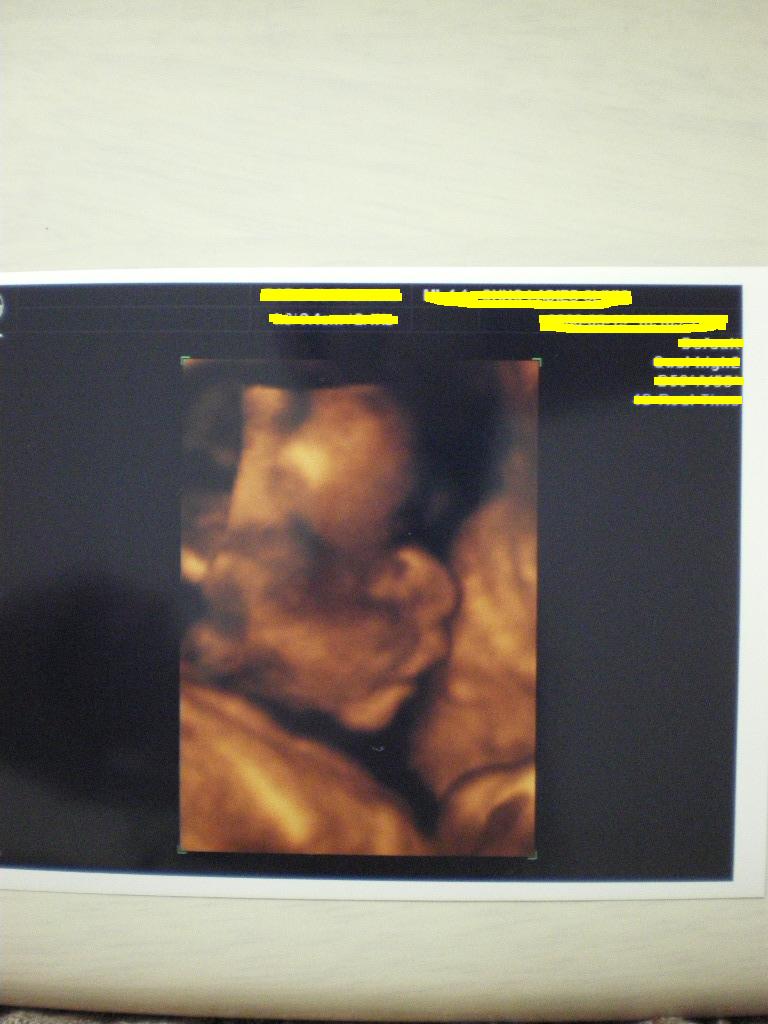

さて、今日は、こまおの検診。

判明いたしました。

こまおは

・・・

女の子でしたwww

でも、生まれるまでは、こまおと言う名で通しますw

思いっきり、胎児ネームミスってるやん!私w

ま、そんなこんなで、こまおはけっこう美人です。

3Dの横顔写真です。

うむ。鼻が高くて、お目目も大きくて、かわいいじゃないの~~~~☆

と、生まれる前からすでに親バカ炸裂のココ猫。

でこっぱちだけど・・・。